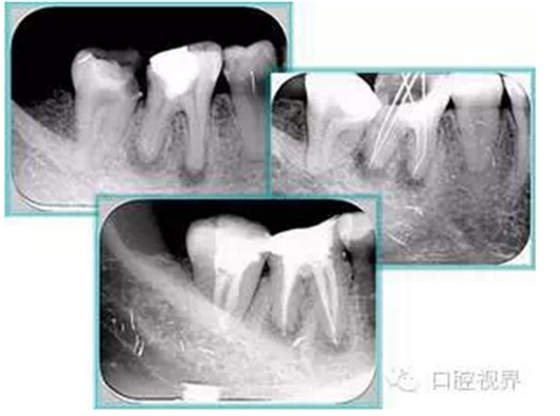

常見有修復性鈣化和增齡性鈣化。下面為根管鈣化 X 線片。

7. 器械折斷

右圖及下圖為器械折斷的 X 線片。箭頭處示折斷器械。

解決方法: ( 1 )取出。 ( 2 )通過。 ( 3 )重新確定工作長度,充填。 ( 4 )根尖手術。

器械折斷可以不用取出,取出的原因多是患者心理因素。留在里面的器械關鍵是進行消毒,預防性使用抗感染藥物,預防感染。

右圖箭頭處示臺階形成。